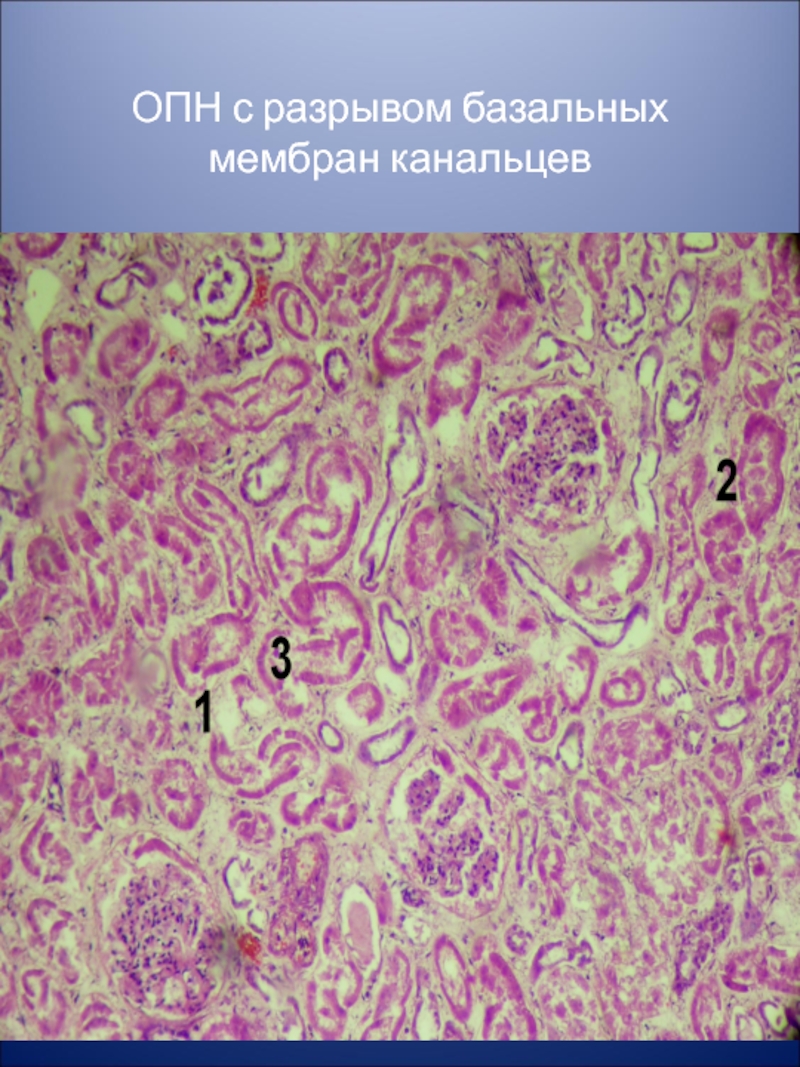

Механизм остро го диффузного гломерулонефрита